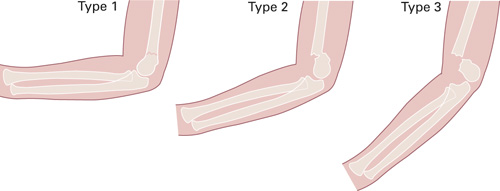

Suprakondylære humerusfrakturer hos barn klassifiseres i dag etter Gartlands klassifikasjon (fig 1) (8). Denne klassifikasjonen har god intra- og interobservatør reliabilitet (9). Gartland type 1 er en udislokert fraktur. Type 2 er en dislokert fraktur med intakt bakre cortex. Disse frakturene er av ren ekstensjonstype, ettersom den posteriore cortex stabiliserer bruddet i rotasjon. Type 3 er en helt dislokert fraktur uten kontakt mellom bruddfragmentene og har ofte rotasjonsfeilstilling i tillegg til ekstensjonsfeilstilling. Disse bruddene er assosiert med nevrovaskulær skade. Det er rapportert pulsløs ekstremitet i opptil 20 % av Gartland type 3-frakturer (4).